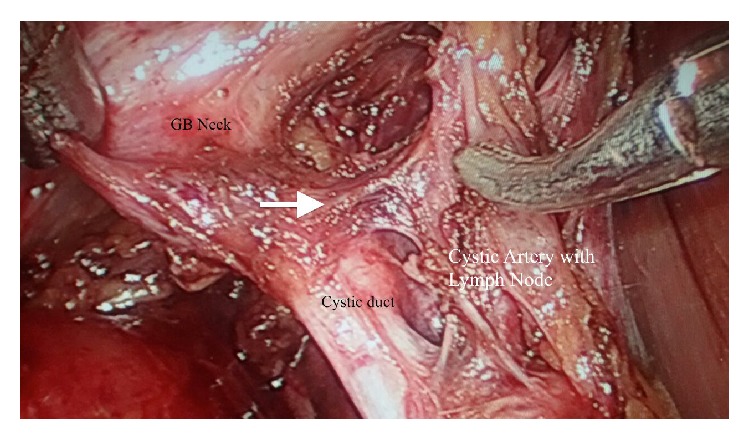

Uncontrolled arterial bleeding during laparoscopic cholecystectomy is a serious problem and may increase the risk of bile duct damage. Therefore, accurate identification of the anatomy of the cystic artery is very important. Cystic artery is notoriously known to have a highly variable branching pattern. We reviewed the anatomy of the cystic artery and its branch to cystic duct as seen through the video laparoscope. A single artery to cystic duct with the classical "H-configuration" was demonstrated in 161 (91.47%) patients. This branch may cause troublesome bleeding during laparoscopic dissection in the hepatobiliary triangle. Careful identification of artery to cystic duct is helpful in the proper dissection of Calot's triangle as it reduces the chances of hemorrhage and thus may also be helpful in prevention of extrahepatic biliary radical injuries.